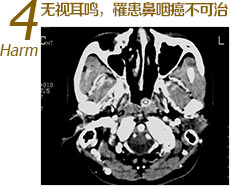

中耳肿瘤等高危疾病的先兆

中耳肿瘤等高危疾病的先兆耳鸣也是某些高危疾病的早中期症状之一,中耳肿瘤(如鼓室球体瘤和颈静脉球体瘤)、桥小脑角肿瘤如鼻咽癌、神经紊乱、脑供血缺乏、糖尿病等,若持续耳鸣应当及早就医…>>详细了解